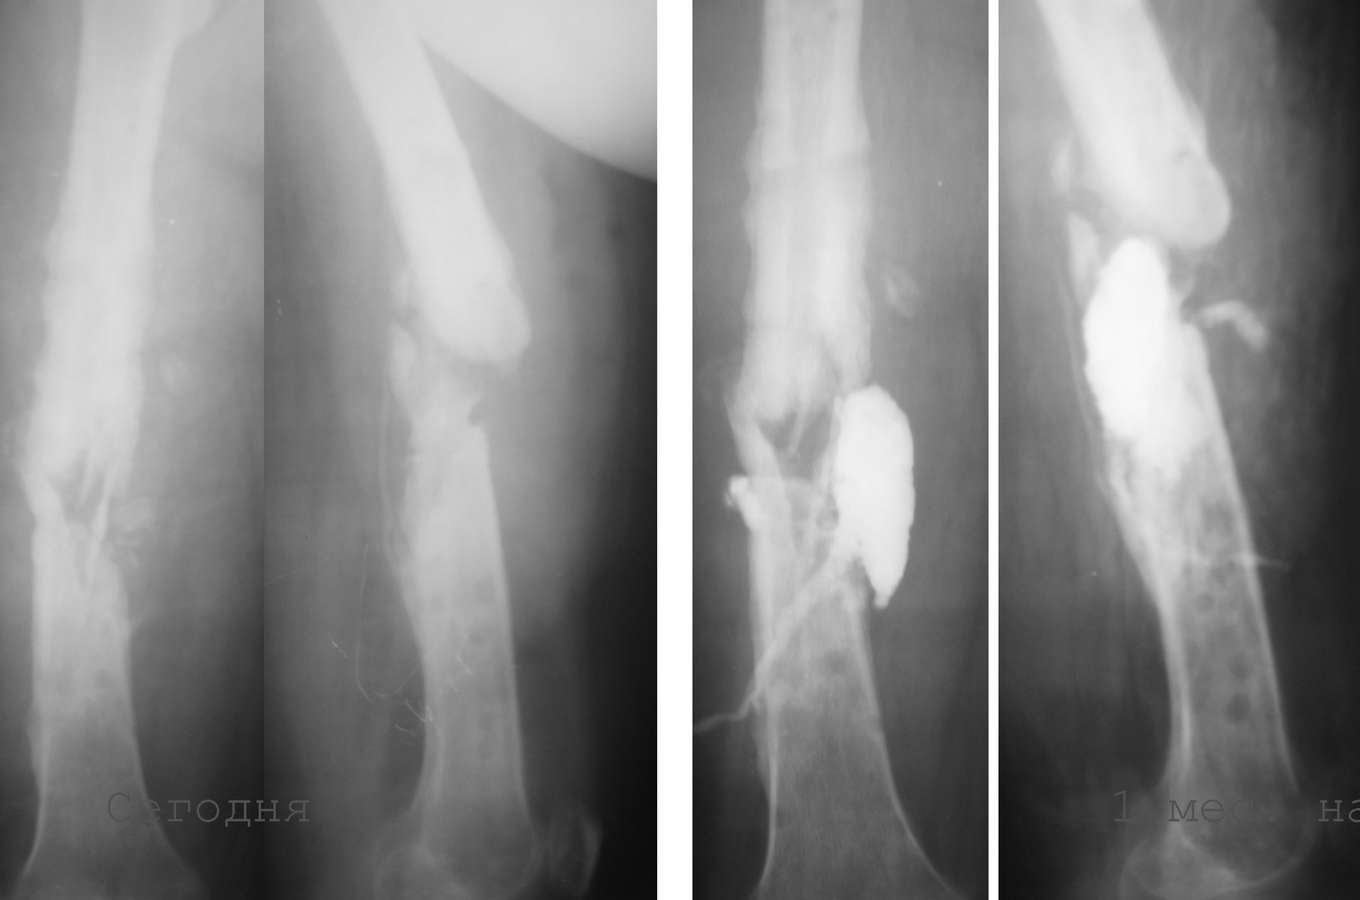

1. 14 мес назад (летом 2008 г)- перелом бедра, оскольчатый, закрытый. Интрамедуллярныйостеосинтез гвоздем Кюнчера, несостоятельная фиксация, поэтому дополнили кокситом.

2. Через 4 мес. ввиду отсутствия перспектив сращения - я выполнил остеосинтез аппаратом Илизарова. В отдельные периоды была надежда наконсолидацию. В аппарате 6-7 мес, постоянные выделения в области стержня - сняли аппарат.

3. 2 мес. ходит с лонгетой, имеется патологическая подвижность. В течение месяца после снятия сохранялись выделения из отверстия, где был стержень, температура до 38, иногда отсутствовала. Сделал фистулу с уверенностью, что это стержневой остеомиелит.

Но контраст ушел в зону перелома, и эвакуировал около 20 мл лизированной крови (без гноя).